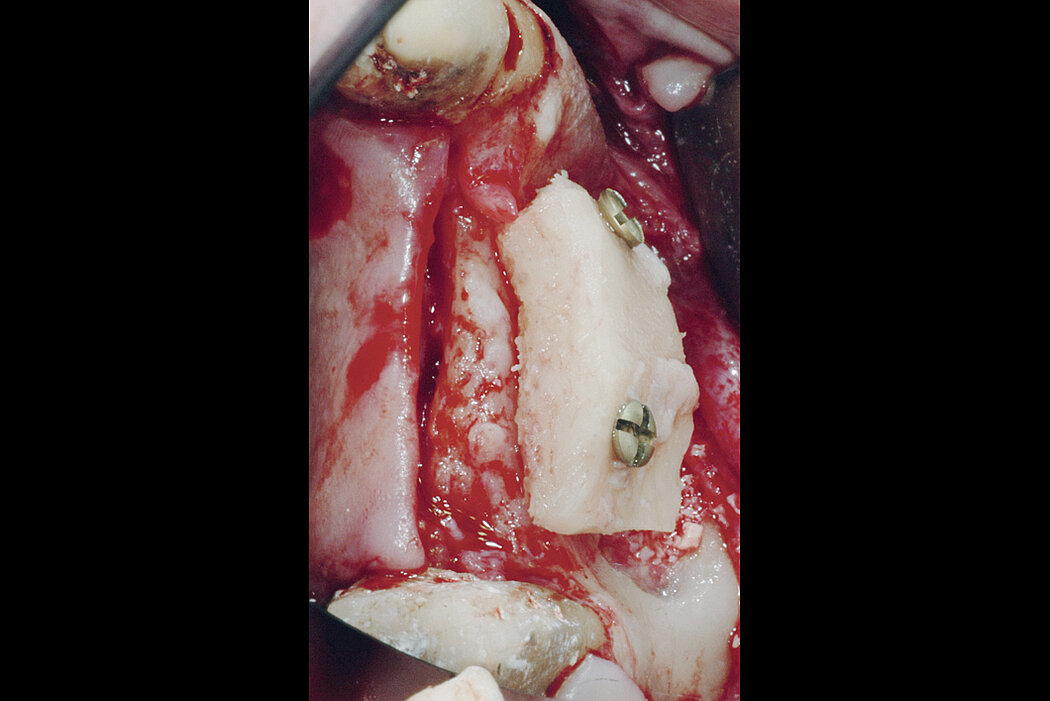

Augmentation with bone blocks

Autogenous bone blocks are the material of choice to compensate insufficient bone height. Resorption, however, can result in functional and aesthetic complications.

Contouring the bone block with slow resorbing Geistlich Bio-Oss® bone substitute and covering the augmented area with a Geistlich Bio-Gide® collagen barrier reduces graft shrinkage. The volume of the augmented ridge remains stable1.